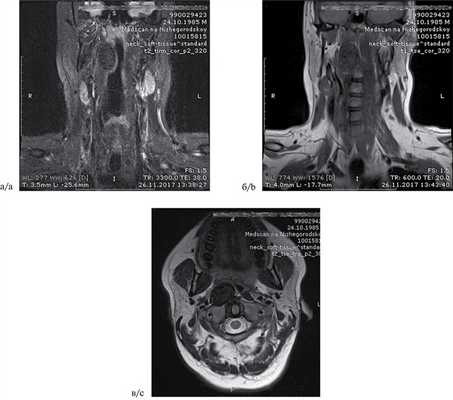

По данным ультразвукового исследования, шейные лимфатические узлы не увеличены. На магнитно-резонансной томограмме (МРТ) на уровне мягкого неба, паравертебрально справа, под длинной мышцей головы определяется дополнительное образование, с гипоинтенсивной структурой во всех последовательностях, умеренным накоплением контрастного препарата, без признаков ограничения диффузии, размером 29×37×22 мм. Сзади новообразование прилежит к правым отделам дуги СI и правым отделам тела СII, структура позвонков в этих областях не изменена, определяется распространение новообразования в пространство между позвонками СI, СII, отмечается объемное воздействие новообразования на правую длинную мышцу головы — мышца истончена, просвет носоглотки в правых отделах сужен. Признаки экспансивного роста образования отсутствуют (рис. 1). Рис. 1. МРТ мягких тканей шеи пациента Н., 30 лет, с фиброзной гистиоцитомой заглоточного пространства. а — фронтальная проекция; б — аксиальная проекция; в — фронтальная проекция с контрастным усилением.